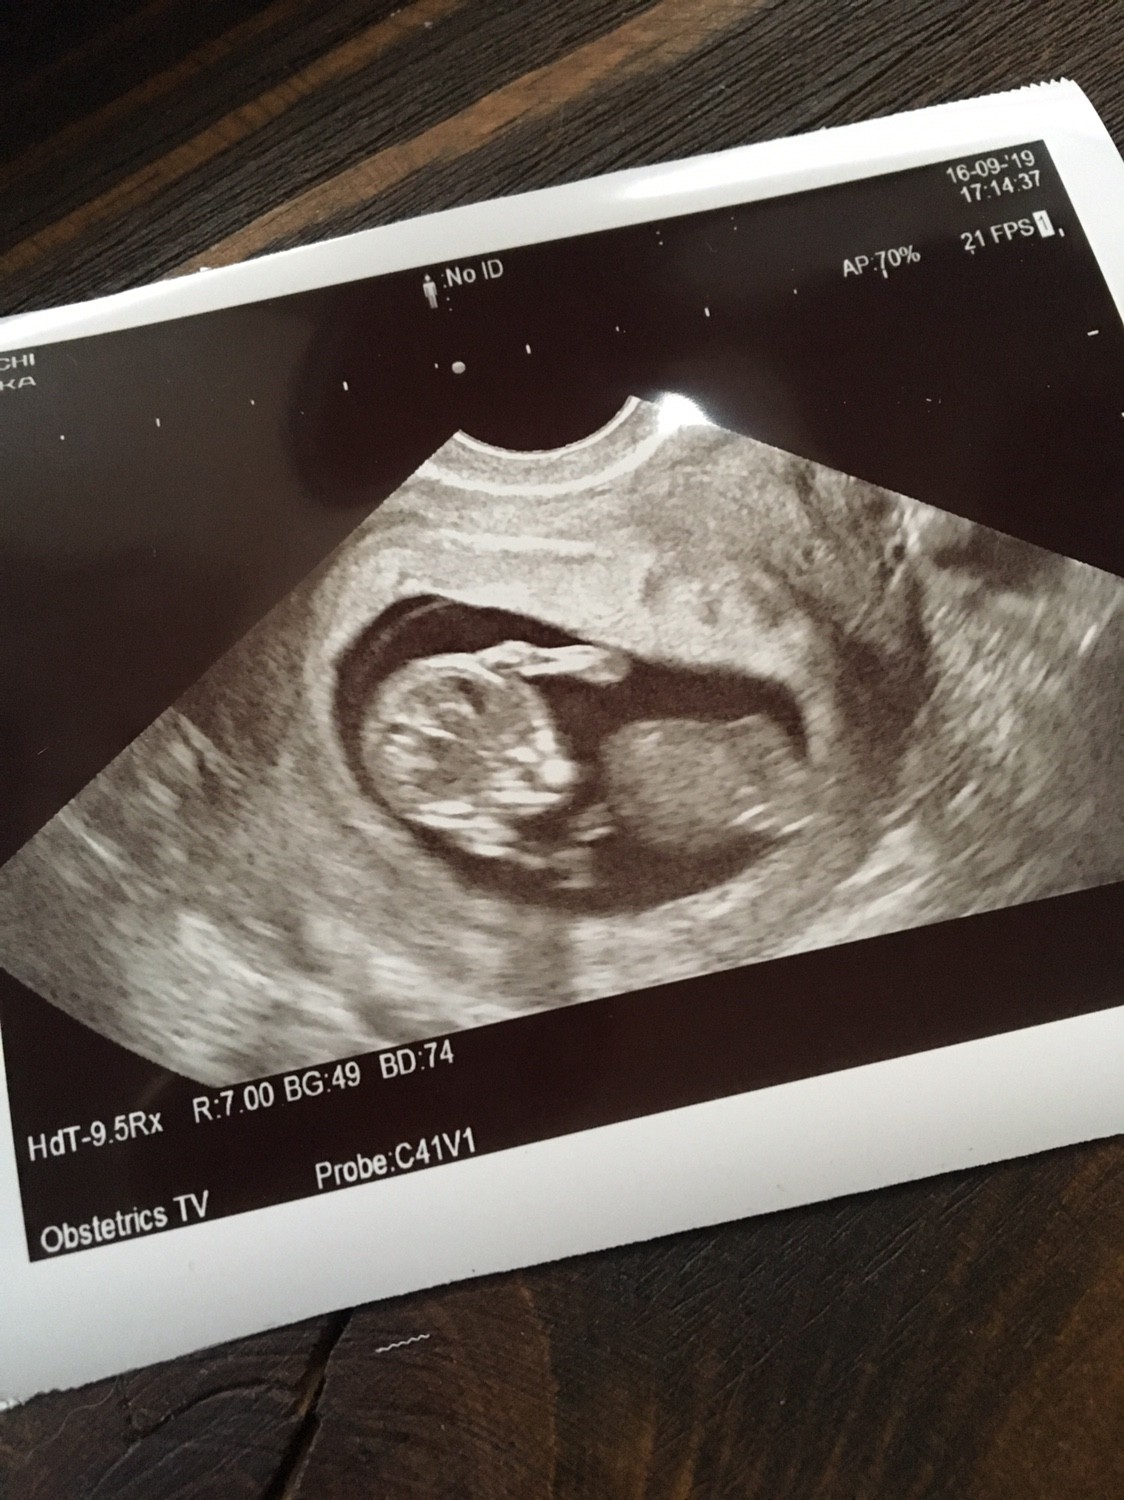

Hej! I ja dziś byłam na wizycie :) dziś zaczęty 11 tydzień, dzidzia 4,6cm. Ale super było widzieć jak dzidziuś się rusza! Zobacz załącznik 1023195